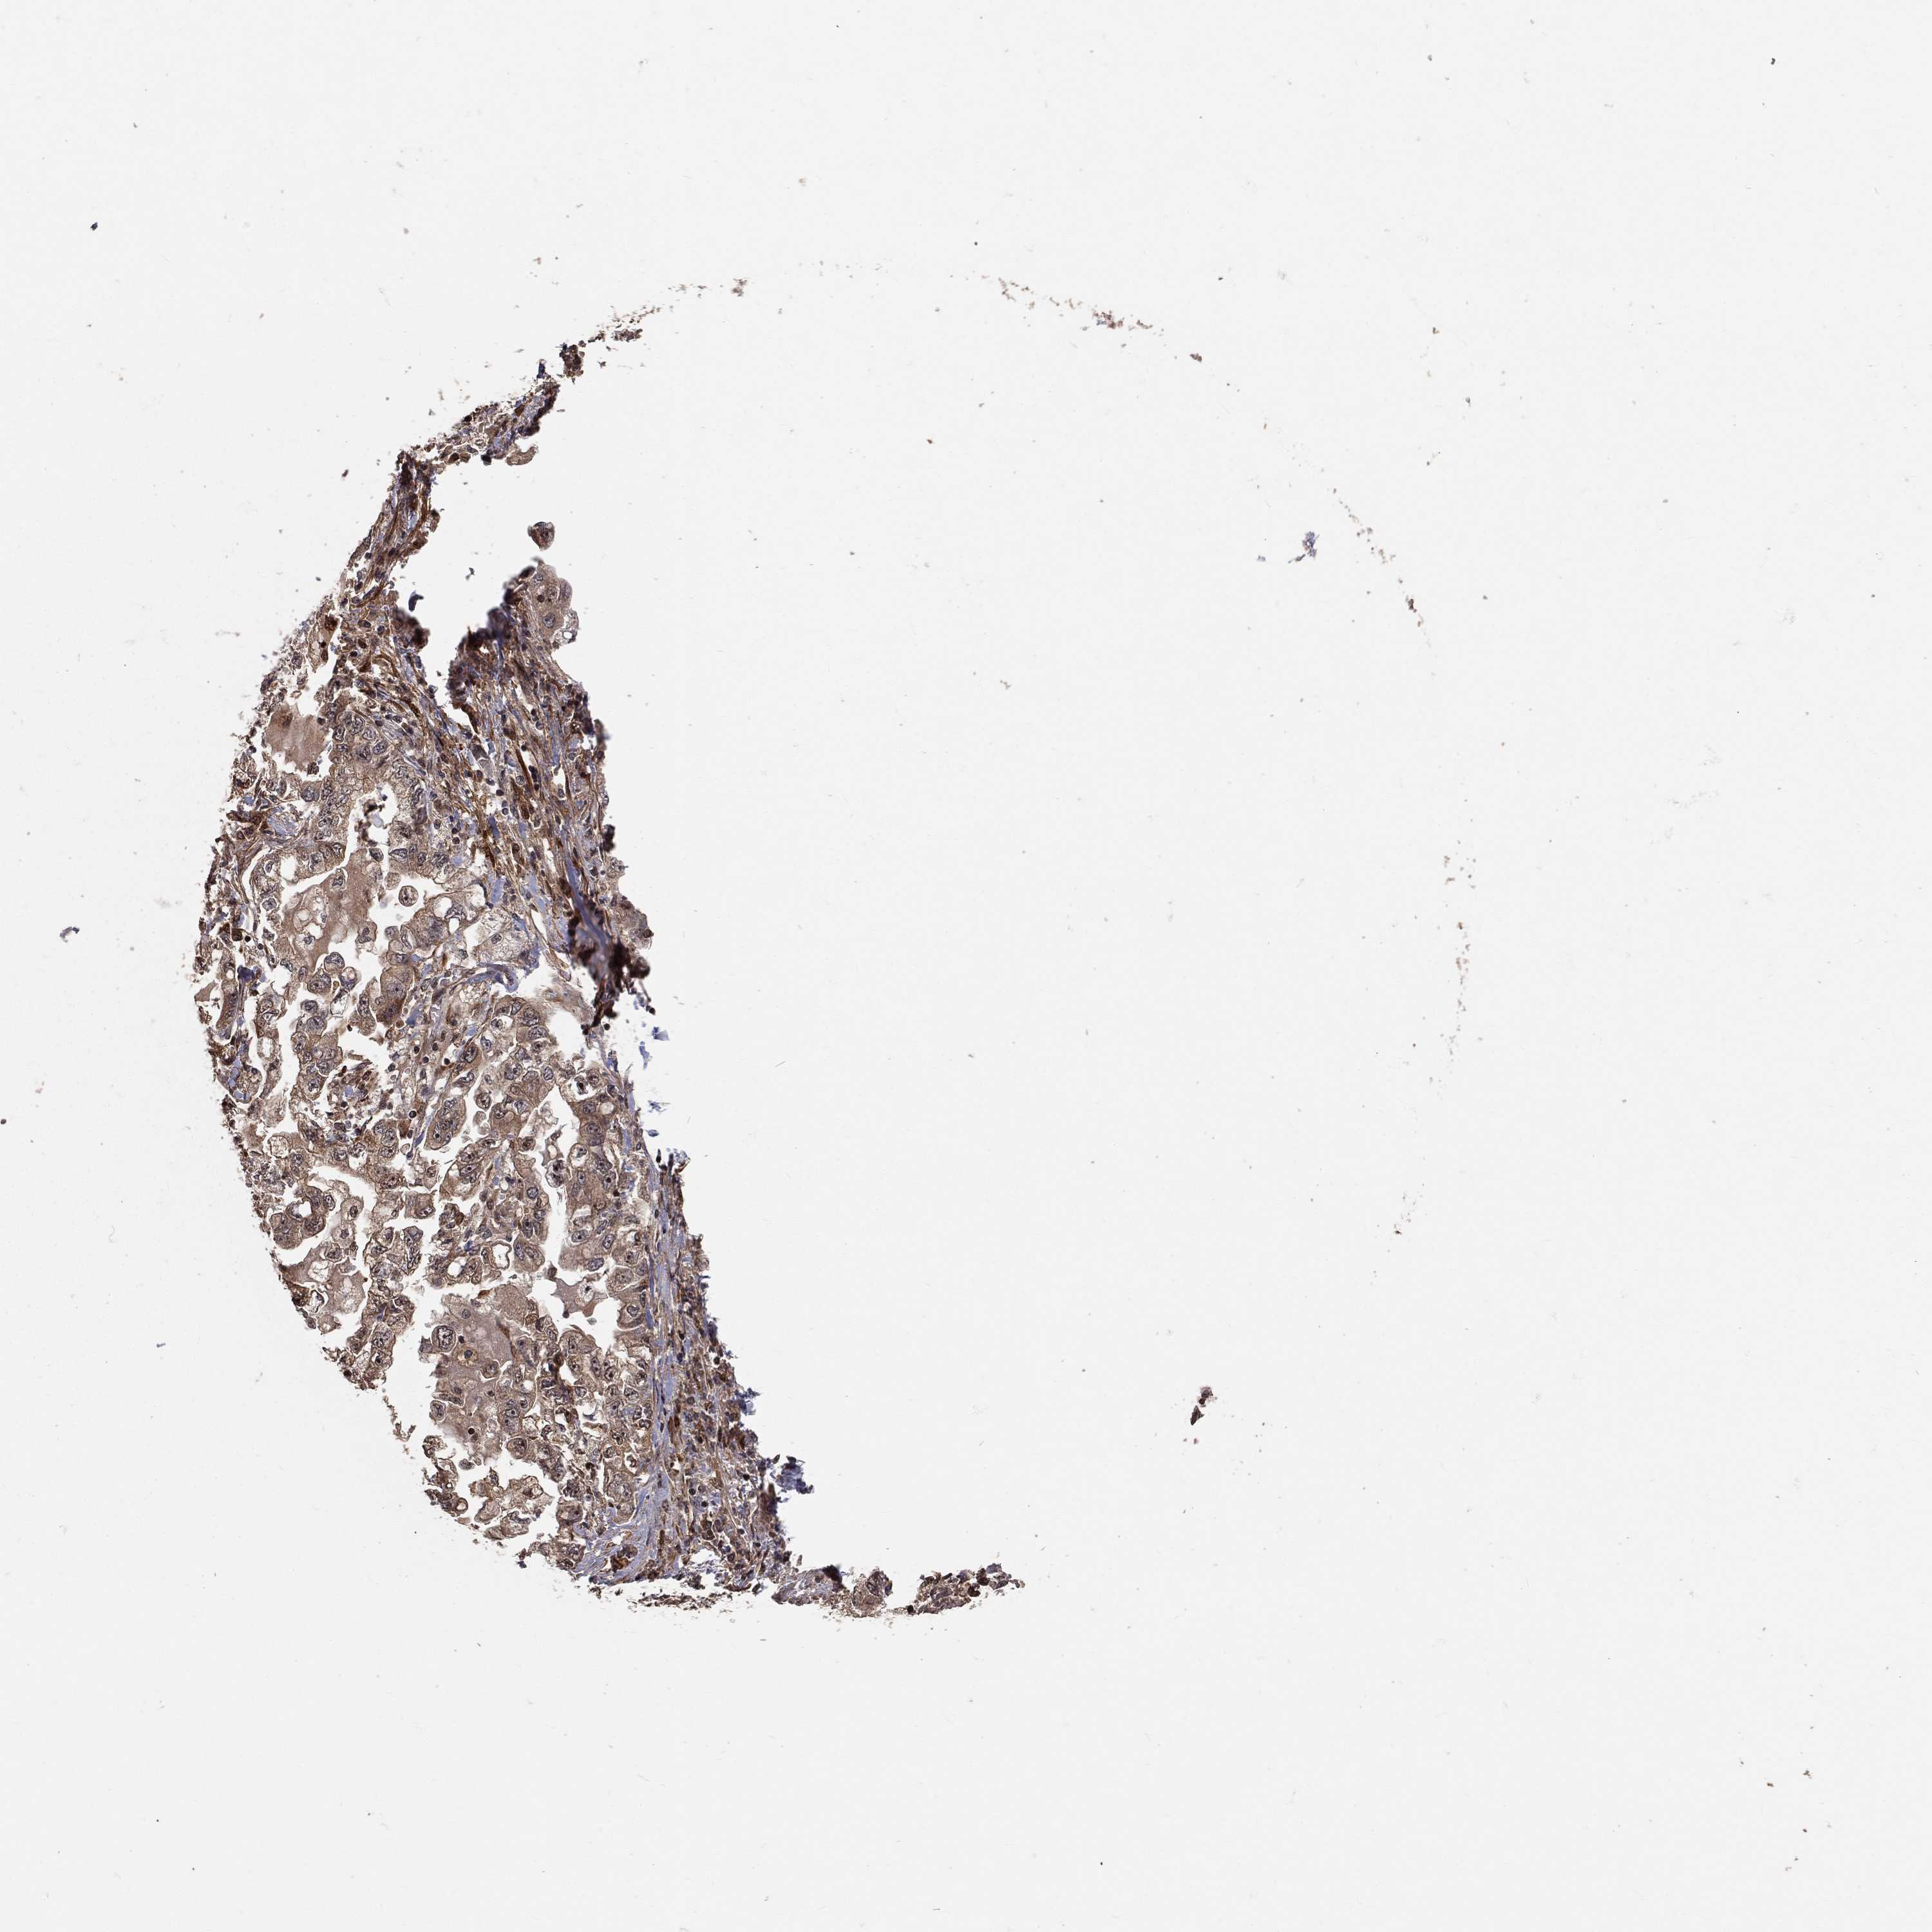

STOMACH CANCER - Protein expressioni

A mouse-over function shows sample information and annotation data. Click on an image to view it in a full screen mode. Samples can be filtered based on level of antibody staining by selecting one or several of the following categories: high, medium, low and not detected. The assay and annotation is described here.

Note that samples used for immunohistochemistry by the Human Protein Atlas do not correspond to samples in the TCGA dataset.

Antibody stainingi

Antibody staining in the annotated cell types in the current human tissue is reported as not detected, low, medium, or high, based on conventional immunohistochemistry profiling in selected tissues. This score is based on the combination of the staining intensity and fraction of stained cells.

Each image is clickable and will lead to virtual microscopy that enables deeper exploration of all samples and also displays staining intensity scores, fraction scores and subcellular localization as well as patient and tissue information for each sample.

Adenocarcinoma, NOS

Adenocarcinoma, High grade